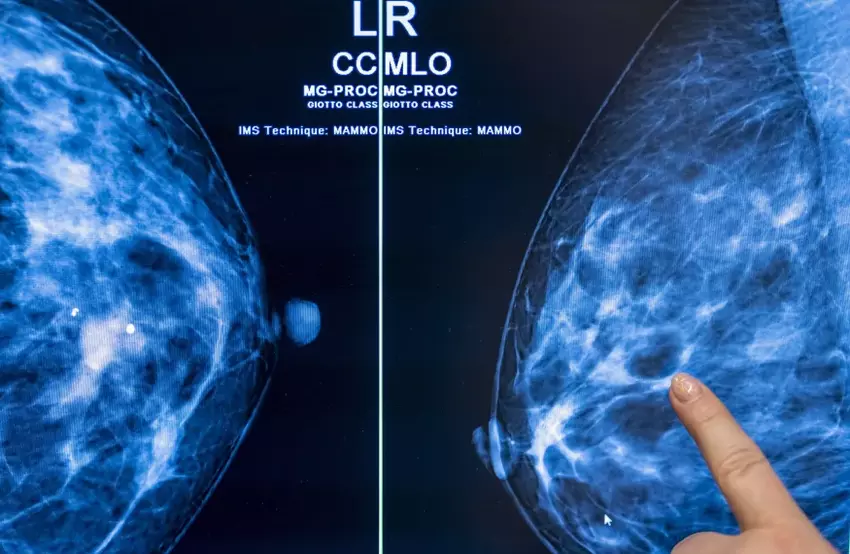

Kankerscreening met kunstmatige intelligentie kan werklast radiologen halveren - onderzoek

Het gebruik van kunstmatige intelligentie bij kankerscreening op basis van mammografie zou de werklast van de radioloog veilig met bijna de helft kunnen verminderen zonder het risico te lopen dat het aantal fout-positieven toeneemt.

In het onderzoek, dat werd uitgevoerd door een team wetenschappers van de Universiteit van Lund in Zweden, werden 80.033 vrouwen gedurende iets meer dan een jaar gevolgd. Van de 39.996 patiënten die willekeurig werden toegewezen aan borstkankerscreenings met AI, bleek 28% een kankergezwel te hebben.

Van de overige 40.024 patiënten die conventionele screening ondergingen, werd slechts in 25% van de gevallen kanker ontdekt.

Het percentage fout-positieve uitslagen voor zowel AI als conventionele screening was 1,5 procent. Van cruciaal belang is dat radiologen die met AI werkten 36.886 screenings minder hoefden te beoordelen dan hun collega's. Dit verminderde hun werklast met 44%. Dit verminderde hun werklast met 44%.

"Door AI ondersteunde mammografiescreening resulteerde in een vergelijkbaar kankerdetectiepercentage vergeleken met standaard dubbel lezen, met een aanzienlijk lagere werklast bij het screenen, wat aangeeft dat het gebruik van AI bij mammografiescreening veilig is", concludeerde het onderzoek.